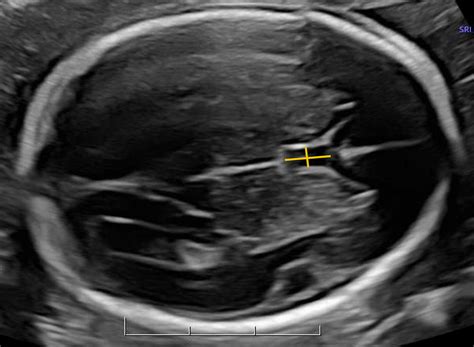

The Cavum Septi Pellucidi is a small, fluid-filled space located between the two leaflets of the septum pellucidum. The septum pellucidum is a thin, triangular, double membrane that separates the lateral ventricles of the brain. During normal fetal development, these two layers are separated by a space, which is the CSP.

Most people discover they have a Cavum Septi Pellucidi during an MRI or CT scan performed for completely unrelated reasons, such as monitoring for migraines, concussion evaluation, or routine check-ups. Because it is often detected on modern imaging, it is frequently classified as a normal anatomical variant rather than a pathology.

The prevalence of a persistent CSP in the adult population is estimated to be between 1% and 3%, though some studies suggest it may be higher in certain demographics. Its appearance on imaging is distinct, typically appearing as a midline, fluid-filled structure that sits between the frontal horns of the lateral ventricles. Radiologists are well-trained to identify this feature and distinguish it from other, more concerning brain cysts or lesions.